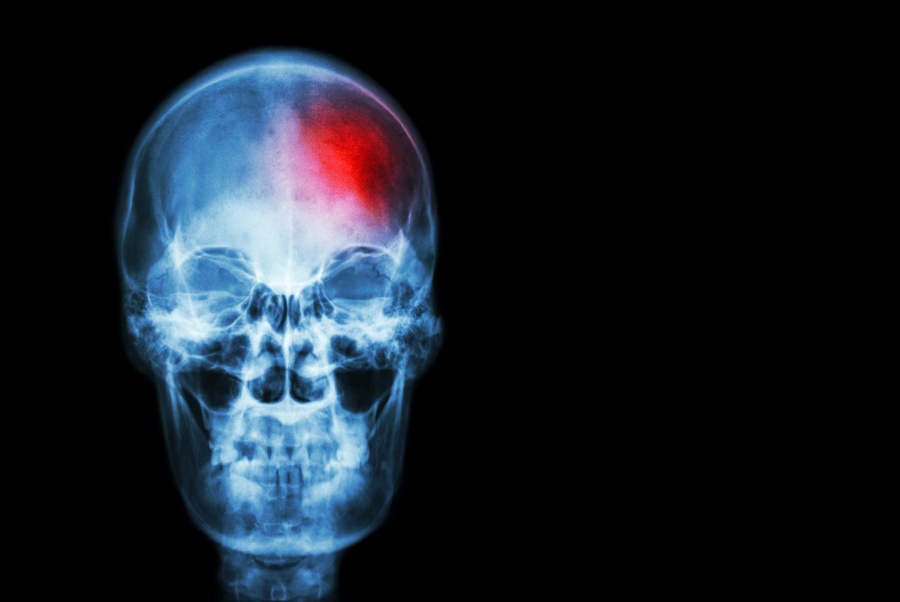

Udar mózgu - przyczyny i leczenie. Czy udar mózgu może wystąpić u młodych ludzi?

Udar mózgu stanowi dla pacjenta śmiertelne zagrożenie. W przypadku jego wystąpienia najważniejsza jest szybka reakcja i niezwłoczny kontakt z pogotowiem ratunkowym. Jak rozpoznać pierwsze objawy udaru mózgu? Czy udar może wystąpić także u młodych osób?

Udar mózgu utożsamiany jest z obumarciem jakiejś części tego narządu, do czego dochodzi na skutek niewystarczającego zaopatrzenia tkanek w krew. Taki stan, w zależności od części mózgu objętego niedokrwieniem, doprowadza do upośledzenia określonych funkcji neurologicznych. Ze względu na mechanizm powstawania udaru rozróżnia się udar krwotoczny i udar niedokrwienny.

Udar krwotoczny

Powstaje w wyniku uszkodzenia ściany tętnicy i wylewu krwi do okolicznych tkanek. W efekcie krew nie dociera do tkanek mózgu, co skutkuje powstaniem obszaru niedokrwienia. Ponadto, krew opuszczająca pękniętą tętnicę powoduje liczne uszkodzenia i wzrost ciśnienia wewnątrzczaszkowego.

Udar niedokrwienny

Dochodzi do niego na skutek zaburzenia drożności naczynia, przez co przepływ krwi zostaje ograniczony lub całkowicie zablokowany. Najczęstszą przyczyną udaru niedokrwiennego jest miażdżyca tętnic mózgowych lub zator, spowodowany m.in. przez zaburzenia krzepnięcia krwi lub powstanie skrzeplin pochodzenia sercowego.